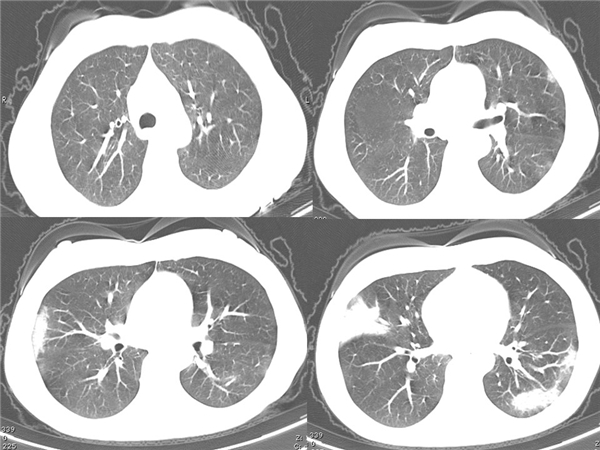

【病例分享】新型冠狀病毒感染肺部CT影像4例(常德市第一人民醫(yī)院)